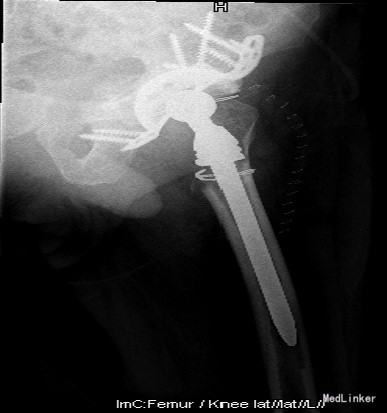

诊断:1.左侧THA术后假体松动、聚乙烯内衬磨损、炎性假瘤形成 2.左侧THA术后髋臼及股骨近端骨溶解 3.左侧THA术后髋臼及股骨近端骨缺损(髋臼AAOS III型 股骨Paprosky II型) 4.右髋重度骨关节炎 5.高血压 (2期 高危) 治疗:完善检查,调整患者全身条件后在全麻下行左侧全髋关节假体取出+炎性假瘤切除+异体骨植骨+髋臼重建+人工全髋关节翻修术,术中发现:左髋关节囊后外侧炎性假瘤形成,与关节腔相通,内有大量咖啡色混浊液体,髋臼及股骨近端骨溶解导致骨缺损,以髋臼前壁及下壁和股骨近端严重,小转子消失,关节腔周围大量炎性坏死组织。髋臼假体松动。术中安放左侧Zimmer64mmCage,并用8枚不同长度螺钉固定可靠,Cage内放骨水泥后安放外径59mm,内径28mm聚乙烯内衬并调整前倾及外展角度合适,股骨侧安放12#加长股骨柄,28mm直径、+1.5颈长陶瓷股骨头。